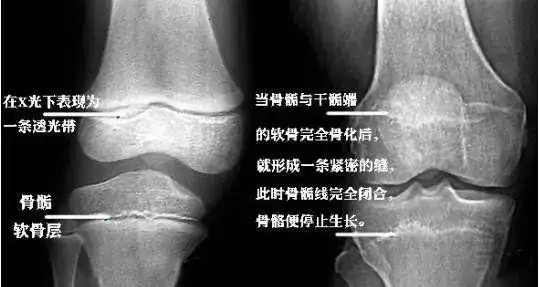

一种我们叫软骨生长,长骨的末端有一个软骨板,也叫骨骺板

骨骺损伤(生长板骨折)是儿童时期所独有的骨折类型,也是儿童骨骼损伤

男孩开始长喉结或变声,意味着骨骺线接近闭合了,女孩在月经初潮来后